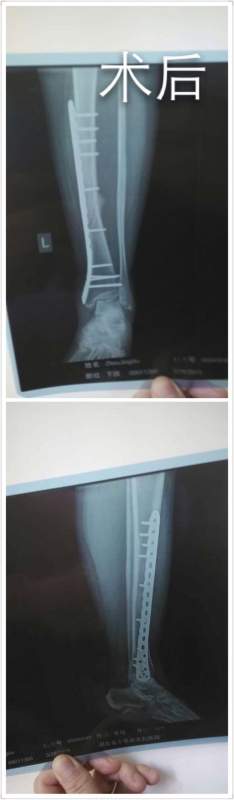

ÂèÂè¹ÇÕÛÁË£¬¹ÇÓúºÏЧ¹ûÒ»Ö±²»ºÃ£¬ÇóÖú ÒÑÓÐ9È˲ÎÓë